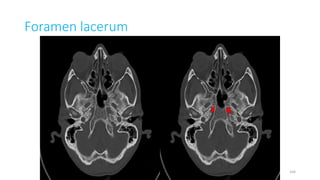

Foramen lacerum

Content

• Artery of pterygoid canal,

• Meningeal branch of ascending

pharyngeal artery,

• Emissary vein

• Nerve of pterygoid

canal through its anterior wall

41